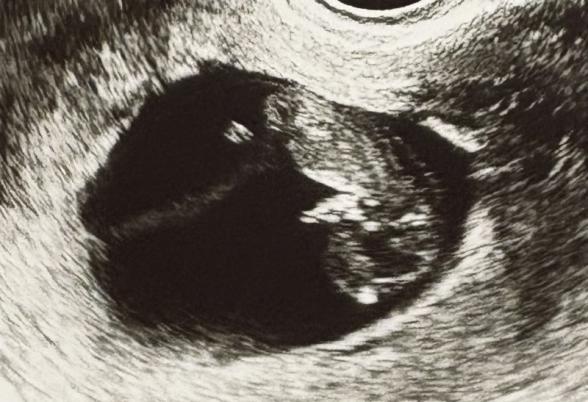

妊娠10週で受けたエコーの写真です。

エコー写真をよく見ると、赤ちゃんの首の後ろあたりに白っぽい線が写っていました。

書かれているように首の後ろのあたりに白っぽい線が写っていますね。

またこのエコー写真では、NTの判定は難しいのではないかと思いました。